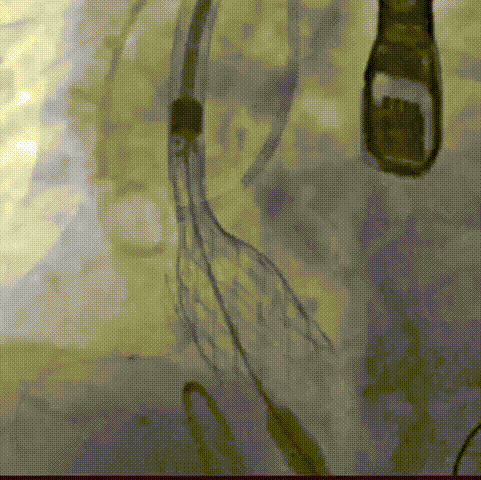

手术过程概览:

主动脉根部造影

20mm球囊预扩,右冠灌注不理想

行烟囱支架技术,瓣膜定位

第一次释放瓣膜,工作位评估

第二次瓣膜释放,工作位评估

瓣膜最终位置

术后即刻评估:

术后压差从86mmHg降至10mmHg无瓣周漏,瓣膜正常工作,血流动力学即刻得到改善。